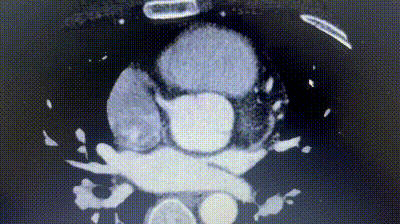

2. Coronary CTA revealed an anomalous origin of the left circumflex artery (LCX) from the right coronary sinus, with a course between the aorta and left atrium.

3. The distance between the ASD and the aberrant LCX was only about 6 mm.

4. There was no aortic rim, and the inferior and posterior rims were relatively soft.

Given the proximity of the defect to the coronary artery, a traditional metal occluder posed a risk of compression, especially during physical exertion. A biodegradable ASD occluder (BDASD-I 18 mm) was therefore selected for its flexibility, lower risk of long-term mechanical injury, and ability to degrade into carbon dioxide and water after completing the closure function.